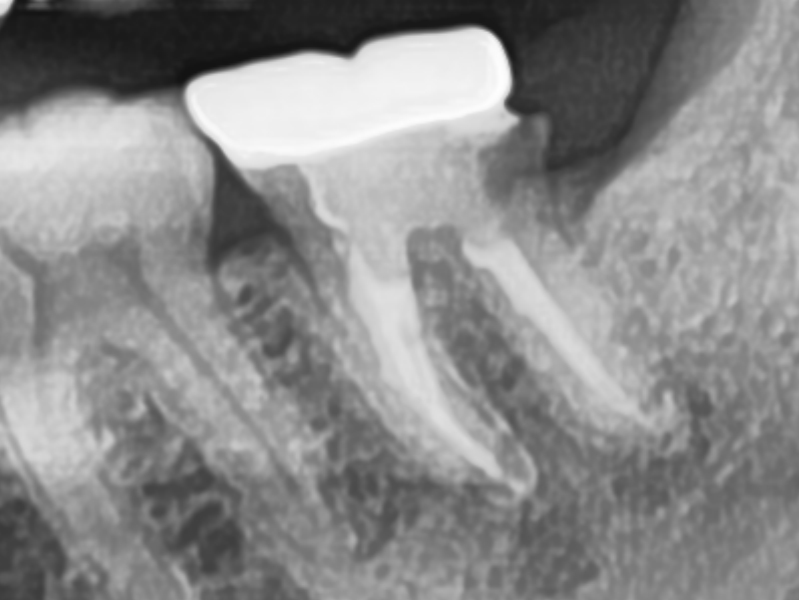

CASE.02 재신경치료

• 재신경치료

기존 신경치료 부분에 염증이 발생하여 재신경치료를 통해 치료

치료전 2023.01.26 / 치료후 2023.02.27